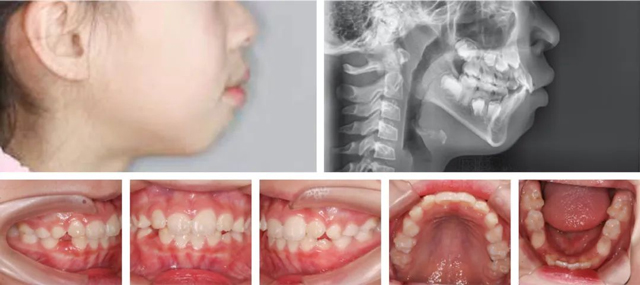

经过详细检查,并结合数字化口扫、CBCT和头颅侧位片,医生发现朵朵侧貌上唇前突,闭唇时颏肌和唇肌紧张,闭嘴困难,出现了“腺样体面容”:上牙前突、唇外翻、唇形肥厚、下巴收紧等。

矫正前

结合口内牙齿、面型、牙片综合评估,孙叡医生制定了一份详尽的矫正方案:扩弓排齐牙齿,解除侧切牙的拥挤状况,给后续恒牙萌出留出位置,并适量内收上颌前牙改善外观。同时还要进行唇肌功能训练,以改善口呼吸的习惯。

矫正半年后